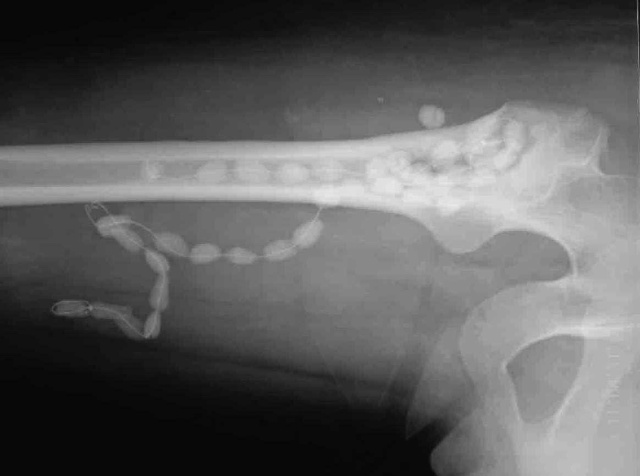

萬(wàn)古霉素骨水泥珠鏈治療感染性骨不連(二)

作者認(rèn)為,放置抗生素鏈珠,首先要確定致病細(xì)菌,對(duì)慶大霉素高敏才能應(yīng)用慶大霉素鏈珠。如果不敏感或者耐藥,或者是微敏,放置慶大霉素鏈珠是不妥當(dāng)?shù)?,即不能達(dá)到消滅細(xì)菌的目的,又增加了新的異物,延誤治療時(shí)間。細(xì)菌培養(yǎng)最好從病灶清除手術(shù)中從骨髓內(nèi)取出的膿液或分泌物進(jìn)行培養(yǎng)為準(zhǔn),因?yàn)閺寞浀纼?nèi)取出的膿液可能會(huì)被污染或者有雜菌感染。如果細(xì)菌對(duì)慶大霉素不敏感怎么辦?作者的經(jīng)驗(yàn)是自制萬(wàn)古霉素鏈珠。萬(wàn)古霉素可以殺滅許多耐藥菌不必多說(shuō)。在20克慶大霉素骨水泥粉劑中可以加入1.6克-2.4克萬(wàn)古霉素粉劑,充分?jǐn)嚢韬蠹尤胍后w單體,進(jìn)入面團(tuán)期后制成黃豆大小顆粒,用雙股細(xì)鋼絲穿入制備成鏈珠,待固化即可使用.對(duì)于骨髓炎萬(wàn)古霉素鏈珠一定要放在骨髓腔內(nèi)或病變清除后的骨床上,這樣抗菌素緩慢釋放后才可以有效達(dá)到目的.我們的經(jīng)驗(yàn)是用軟鉆擴(kuò)髓,清除骨髓腔內(nèi)感染性肉芽組織,脈沖槍沖洗,然后將萬(wàn)古霉素鏈珠盡可能深的放在骨髓腔內(nèi)。尺骨骨髓炎骨不連,將萬(wàn)古霉素骨水泥放在病變清除后的骨床,作進(jìn)一步植骨手術(shù)的填充劑,為2期植骨內(nèi)固定手術(shù)創(chuàng)造了條件.作者采用這種方法治療骨髓炎,感染性骨不連50余例,均痊愈。.